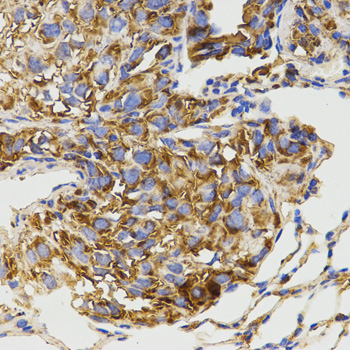

Immunohistochemistry of paraffin-embedded human ovarian cancer using GRM8 antibody.